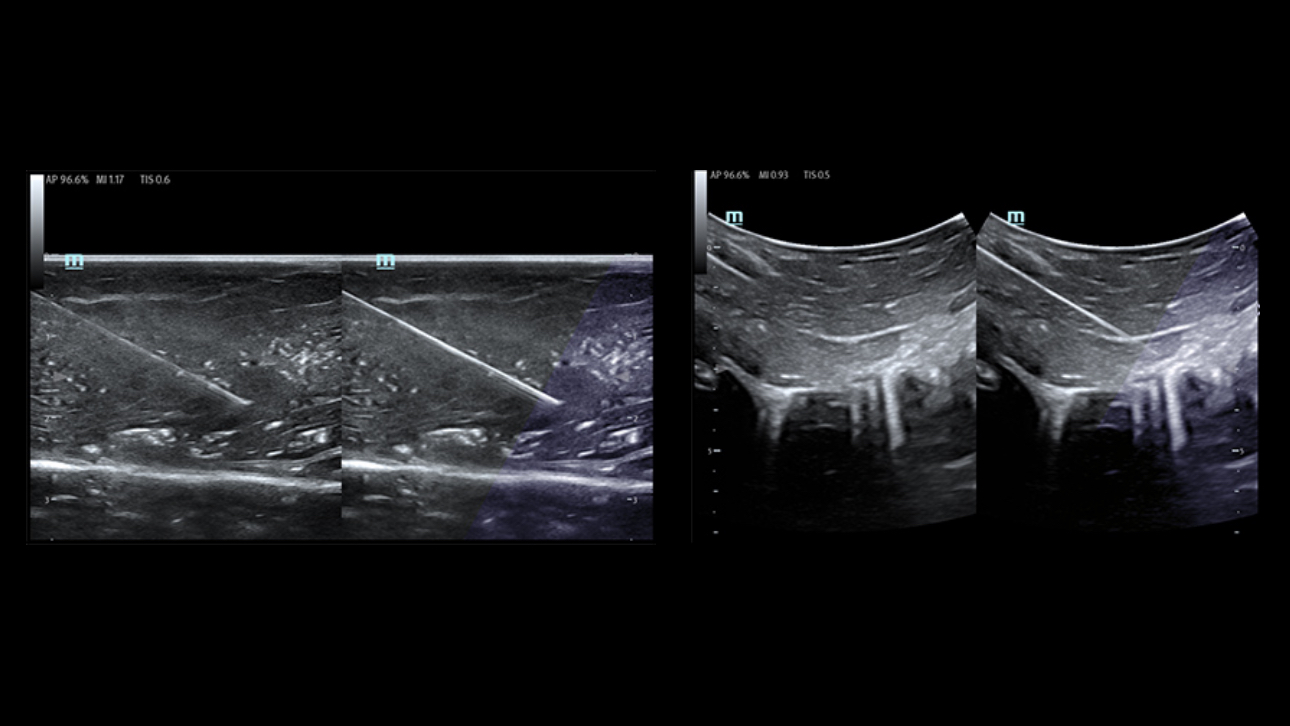

L'├®chographe TE9 a ├®t├® con?u pour faciliter les soins et ├®tendre les capacit├®s d'imagerie pour lŌĆÖanesth├®sie, les urgences et les soins intensifs. Gr?ce ├Ā ses fonctions avanc├®es, son grand ├®cran tactile et sa technologie d'imagerie sup├®rieure, l'├®chographe TE9 permet d'am├®liorer l'efficacit├® clinique et dŌĆÖassurer un diagnostic en toute confiance. Gr?ce ├Ā des outils dŌĆÖacquisition et de calculs automatiques, les soignants peuvent obtenir des mesures rapides et reproductibles dans le cadre d'examens et proc├®dures fiables, m├¬me dans des environnements o├╣ le rythme est soutenu.

Solution de ponction par un seul op├®rateur